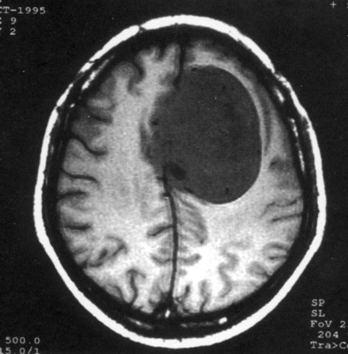

问题 病历摘要:??患者,男,40岁。发作性左下肢抽搐1年余,每次发作3~5分,每周发作1~2次。每次发作后感左下肢乏力,约半日后可自行恢复。既往身体健康。体检:神清,头顶部偏右有局限性骨性隆起(1.5×1.5cm),左鼻唇沟稍浅,伸舌居中。感觉、运动无明显异常。左浅反射减退,左下肢腱反射稍亢进,左Babinski征(-)。 术中下列哪些处理是错误的?提示:脑血管造影示上矢状窦中段闭塞,肿瘤有右脑膜中动脉和大脑前动脉分支供血。

选项 A.切皮前半小时给予抗生素 B.右顶开颅,切口至中线 C.电灼上矢状窦表面出血 D.对横跨在肿瘤表面的中央静脉电凝后切断 E.沿肿瘤和脑组织分界面以食指分离 F.连同肿瘤一起切除相连的矢状窦 G.切除受侵犯的硬膜,以人工脑膜修补 H.去除受侵犯的颅骨,以人工颅骨修补 I.术中静滴德巴金

答案 DE